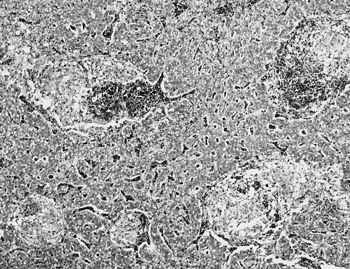

組織学的には,肝臓ではびまん性,小葉中心性に重度の肝細胞壊死・脱落があり,肝細胞の脱落部には赤血球とマクロファージ系細胞が充満していた(図24).中間帯には好酸性の滴状物を容れる球状物やマクロファージ系細胞が散見され,小葉辺縁部では肝細胞の再生,胆管の増生と偽胆管の形成が認められた.好酸性滴状物の同定のために銅,亜鉛,鉄およびマンガンなど微量金属による過酸化反応にともなうNitrotyrosinの免疫組織化学的検出をこころみたが陰性で,PAS反応,PTAH,ベルリンブルーも陰性であった.大脳では,皮質において神経細胞の壊死と神経網の空胞化および血管周囲腔の拡張がみられた.同様に病性鑑定を行った他の1例についても,肝臓と大脳に同様の組織所見が認められた.

図24

小葉中心性に肝細胞の脱落があり,出血をともなっている(HE染色 ×100).